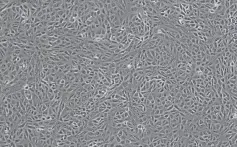

非洲绿猴肾(Vero)细胞

Vero细胞于1962年从非洲成年绿猴肾脏上皮细胞分离而得,属于连续的非整倍体细胞,在疫苗研发和生物制品生产中被广泛使用,同时也是较为理想的病毒感染分子机制研究模型。

Vero细胞较易获取,便于建立细胞库和保存,对培养环境的要求不高,生长速度较快且经过多个分裂周期而不老化,可连续传代。其遗传性状稳定,无外源性污染,恶化概率低,生物安全性较高。同时与正常的哺乳动物细胞不同的是,Vero细胞的干扰素分泌功能有缺陷,被病毒感染后无法分泌干扰素,但具有干扰素受体,人工添加干扰素后细胞仍可以产生反应。

由于Vero细胞对多种病毒敏感度较高,因此被广泛应用于脊髓灰质炎、狂犬病、轮状病毒、天花、出血热、流感等疫苗生产制造中,同时在探究COVID-19的发病机制和治疗方法研究过程中也起到关键作用。